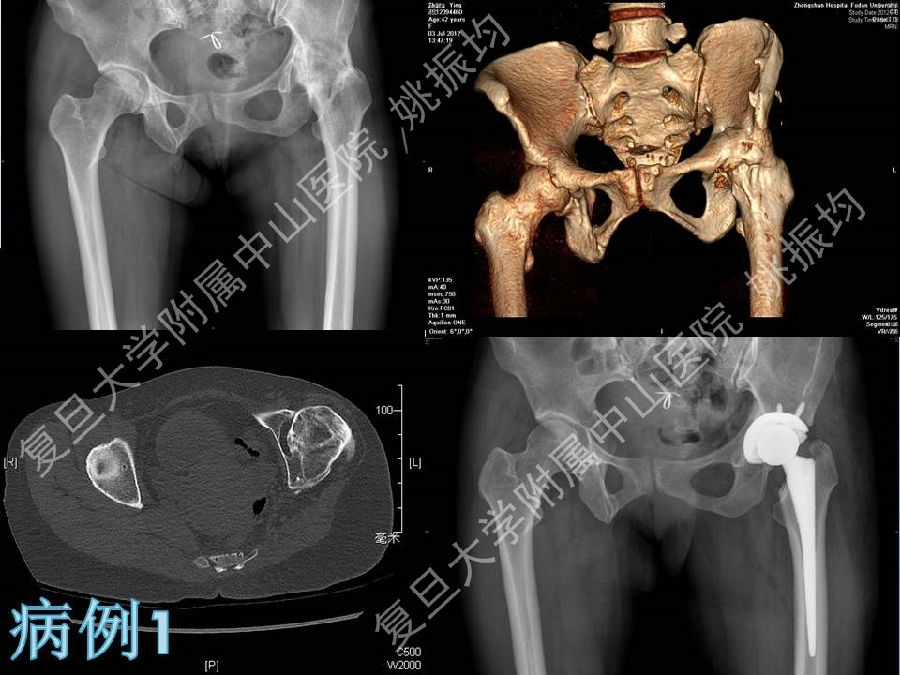

强直性脊柱炎(ankylosing spondylitis, AS)是一种血清学阴性的慢性进行性炎症性疾病,主要侵犯骶髂关节、脊柱和髋关节等。对AS晚期引起的髋关节畸形施行全髋关节置换术,是目前公认的改善关节功能的有效方法.

复旦大学附属中山医院姚振均教授在“强直髋关节的人工关节置换”专题授课中从强直性脊柱炎的患者选择、术前准备、手术技巧、术后护理、病情转归、典型病例分享方面,讲述了他是如何做强制髋关节置换手术的,我们一起来回顾下精彩课件吧!